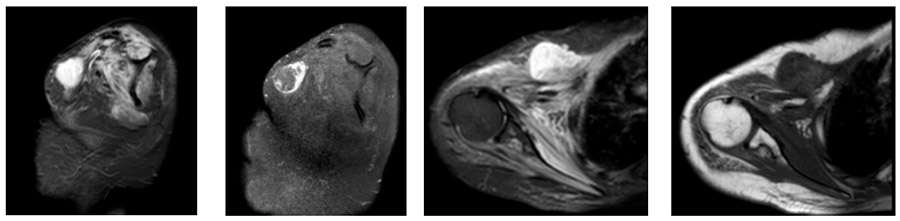

Ameliyat Öncesi: MR’da omuz ön kısımda yerleşmiş düzensiz sınırlı heterojen kitle görülmekte